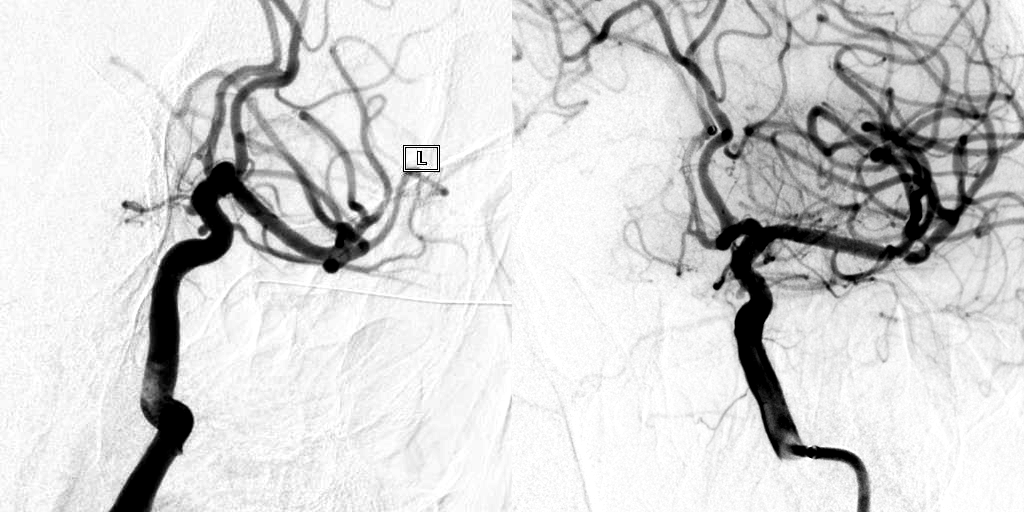

介入科团队在仔细研究影像资料、进行详尽的术前讨论并与家属充分沟通后,制定了周密的手术方案。在麻醉科的密切配合与保障下,手术团队成功为患者实施了微创介入手术。术后影像显示:动脉瘤内造影剂滞留(预示血流隔绝效果良好),支架内血流通畅,支架精细显影并与载瘤血管壁贴合良好。术后患者在神经内科医护团队的精心治疗和护理下顺利康复出院。

动脉瘤密网支架治疗后显示动脉瘤内造影剂滞留,支架内血流通畅

密网支架精细显影,可见支架完全覆盖动脉瘤并与血管壁贴合良好